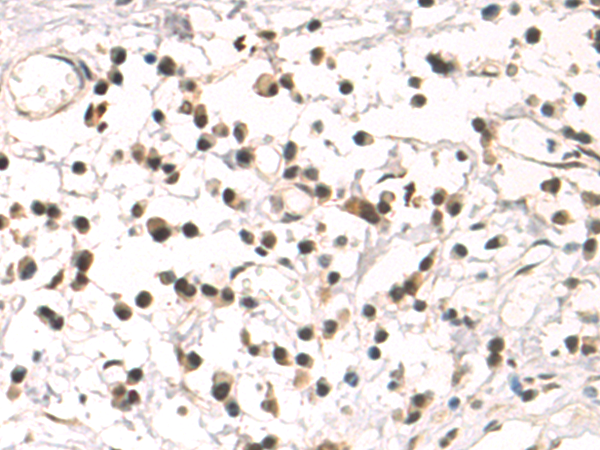

分类: 科研抗体货号: P10356别名: SAMP32应用: IHC反应种属: Human